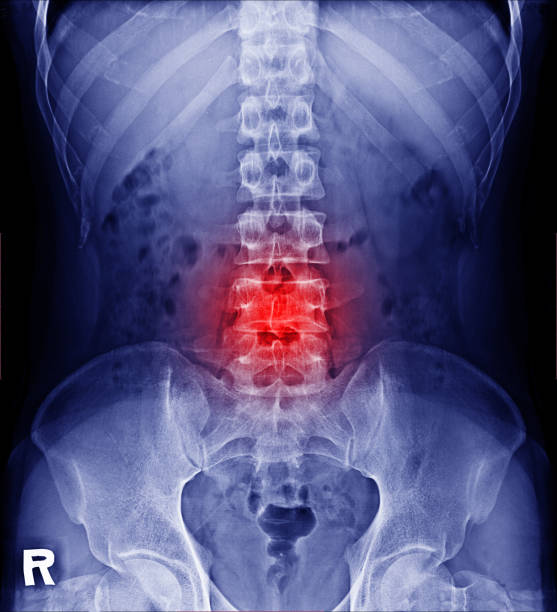

허리디스크 원인

허리디스크 증상

허리디스크 증상은 탈출증의 위치와 심각도에 따라 달라질 수 있습니다. 일반적인 증상은 다음과 같습니다.

1. 허리 통증: 허리 통증(종종 한쪽에만 발생)이 전형적인 증상입니다.